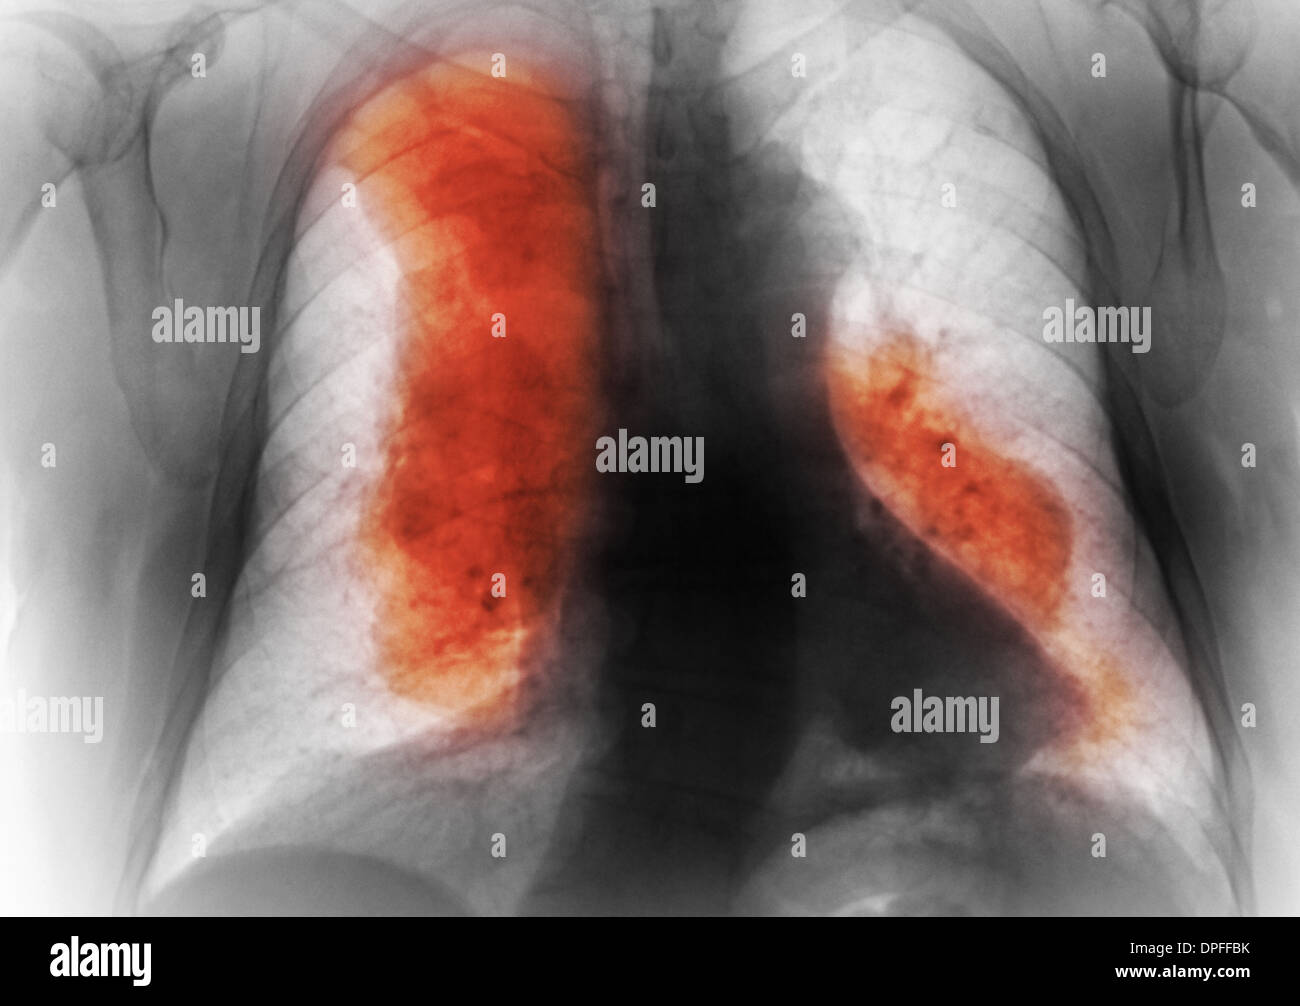

From www.alamy.com

chest xray showing lymphoma cancer Stock Photo Alamy Can A Chest X Ray Diagnose Lymphoma The etiology is unknown but potential. Patients with lymphoma often have ct scans of the neck, chest, abdomen, and pelvis to find out how many lymph nodes are involved, how large they are, and whether internal organs are affected by the disease. The best way to diagnose lymphoma is to perform a biopsy of a lymph. Lymphomas are malignancies that. Can A Chest X Ray Diagnose Lymphoma.